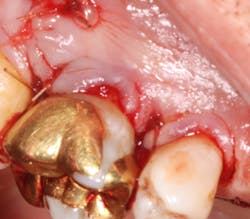

A 69-year-old male with a noncontributory medical history presented with 5 mm of recession, less than 1 mm of attached gingiva, and cervical notching on tooth No. 3. The tooth had an existing gold onlay and was caries-free (figures 1a and 1b). Radiographic analysis showed periodontal bone loss and a radiolucency at the apex of the tooth. The patient denied implant therapy and wanted to save the tooth.

A split- to full-thickness intrasulcular incision was made on the facial of teeth Nos. 2 through 4. Upon completion of flap elevation, an intraosseous cyst associated with the distobuccal root of No. 3 was noted perforating the buccal plate and adherent to the overlying flap (figure 2). A sharp dissection separated the cyst from the flap (figure 3), and the cyst—measuring roughly 1.0 x 0.75 x 0.5 cm—was enucleated intact, leaving an intraosseous defect (figures 4a and 4b).